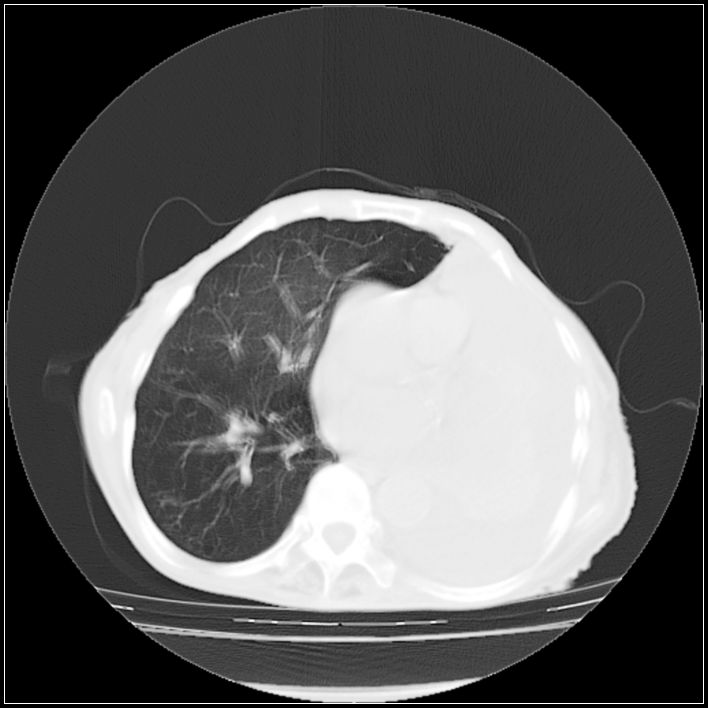

以下是引用ydx_74在2008-5-31 16:08:00的发言:[br]中心性肺癌并左侧肺不张、胸水。

以下是引用影象小辈在2008-5-31 16:25:00的发言:[br]左侧胸腔团状不规则致密影,界欠规整,密度不均匀,其内可见更低密度影及高密度影,并可见包裹性胸腔积液 考虑为1.畸胎瘤 2.肺癌